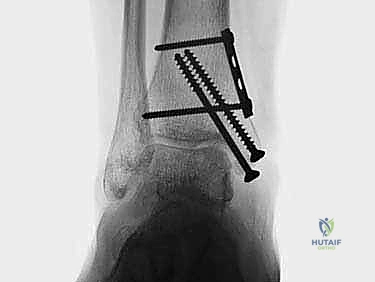

2. الزرع الغضروفي العظمي الذاتي (OATS / Autograft): وهو محور حديثنا والتقنية الذهبية التي يبدع فيها الأستاذ الدكتور محمد هطيف لعلاج الآفات المتوسطة والكبيرة.

الغوص العميق: تقنية الزرع الغضروفي العظمي الذاتي (OATS) خطوة بخطوة

تُعد تقنية OATS (Osteochondral Autograft Transfer System) بمثابة "زراعة أعضاء دقيقة" داخل المفصل. الفكرة الأساسية هي أخذ أسطوانة صغيرة من العظم والغضروف السليم من منطقة لا تحمل وزناً كبيراً في جسم المريض (غالباً من مفصل الركبة)، ونقلها وزرعها في مكان الآفة التالفة في الكاحل.

هذه التقنية توفر "غضروفاً زجاجياً حقيقياً" (Hyaline Cartilage)، وهو نفس نوع الغضروف الأصلي الذي خُلق به الإنسان، مما يضمن متانة وقدرة على تحمل الأوزان لا يوفرها أي علاج آخر.